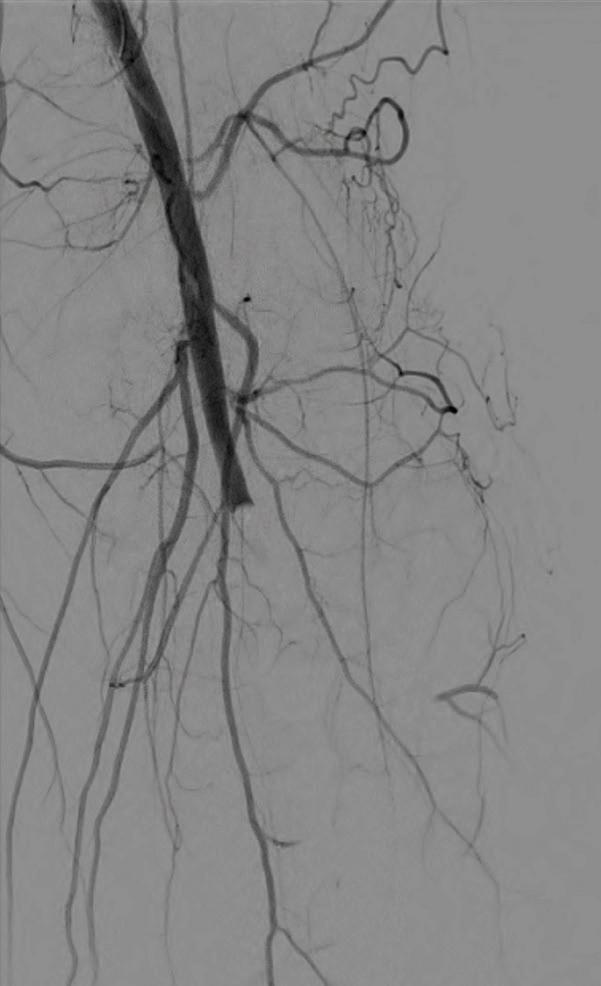

Shockwave E8 3mm x 80mm to the posterior tibial artery

The posterior tibial artery was successfully crossed first. The long-length posterior tibial artery disease was treated with a Shockwave E8 3.0mm x 80mm IVL catheter, with no pre-dilatation required. A total of 200 pulses were delivered along the length of the posterior tibial artery (Figure 3).

Shockwave E8 3mm x 80mm to the peroneal artery

Following this, the peroneal artery occlusion was successfully crossed. The longlength peroneal artery disease was treated with the same Shockwave E8 3mm x 80mm IVL catheter also with no pre-dilatation required. The remaining 200 pulses were

delivered across the length of the peroneal artery disease (Figure 3).